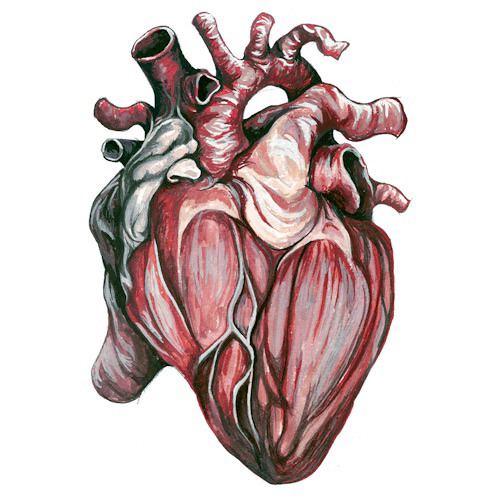

Анатомия здорового сердца: фотографии и иллюстрации